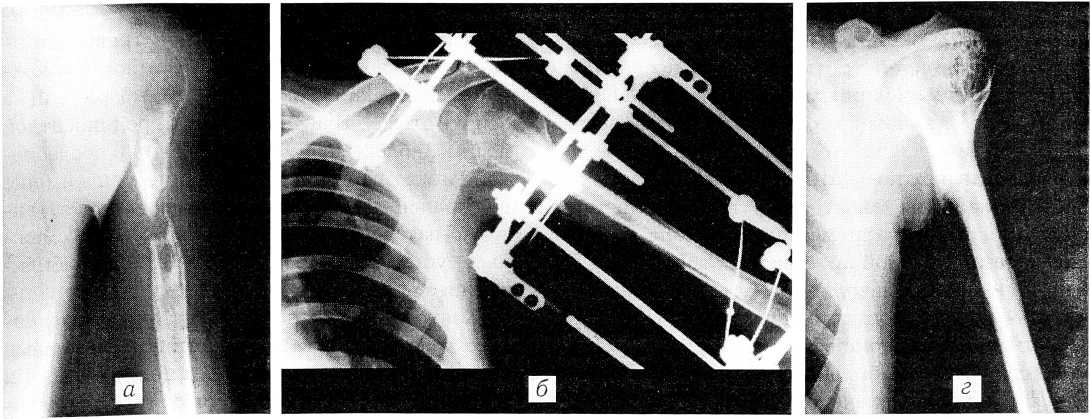

Больной К., 18 лет, поступил в клинику с метадиафизарным дефектом в верхней трети левой плечевой кости. Дефект образовался после сегментарной резекции кости по поводу гигантоклеточной опухоли и был замещен аллотрансплантатом, который, однако, подвергся лизису. Впоследствии больной трижды оперирован (внеочаговый чрескостный остеосинтез, костная аутопластика трансплантатом из подвздошной кости, пластика деминерализованными трансплантатами) без эффекта, трансплантаты лизировались (см. рисунок, а). При осмотре: атрофия мышц плеча и надплечья, укорочение плеча на 3 см, множество рубцов от предыдущих операций, «болтающееся» плечо. 7.04.87 произведена операция — аутопластика дефекта свободным васкуляризированным трансплантатом из малоберцовой кости с «сигнальным» кожным лоскутом, остеосинтез аппаратом Илизарова (см. рисунок, б). Длина трансплантата составила 18 см при дефекте плечевой кости после резекции концов отломков 10 см. Размеры контрольного кожного лоскута — 4×2 см. Трансплантат внедрен интрамедуллярно в отломки плечевой кости. Артериальный анастомоз наложен между артерией трансплантата и плечевой артерией по типу конец в бок, обе сопровождающие вены трансплантата анастомозированы конец в конец с венами на плече. Послеоперационный период протекал без осложнений.

Аппарат снят через 3,5 мес, после полной консолидации трансплантата с реципиентной костью. Какой-либо дополнительной фиксации защитными ортезами впоследствии не проводилось. Через 1,5 мес после снятия аппарата достигнут практически полный объем активных движений в суставах оперированной конечности (см. рисунок, в). Через год после операции больной получил звание кандидата в мастера спорта и выступал за сборную команду своего университета по баскетболу. Через 2 года на рентгенограммах отмечается выраженная гипертрофия трансплантата с формированием непрерывного костномозгового канала и утолщением кортикального слоя (см. рисунок, г). Объем движений в суставах конечности полный, болей в донорской голени нет, рецидива опухоли не выявлено.

Больной К.: а — рентгенограмма левой плечевой кости с дефектом в верхней трети; б — дефект замещен свободным васкуляризированным малоберцовым аутотрансплантатом, наложен аппарат Илизарова; в — функция оперированной конечности через 1,5 мес после снятия аппарата (5 мес после операции); г — рентгенограммы плечевой кости через 2 года после операции (отчетливо видна гипертрофия трансплантата с формированием непрерывного костномозгового канала и утолщением кортикального слоя трансплантата).